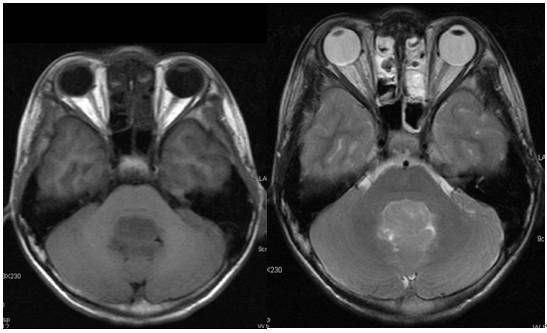

本例患者为第四脑室室管膜瘤,结合患者的术前MRI扫描,我们发现肿瘤累及延髓迷走神经三角。我们推测,手术损伤及术后的水肿均可能损伤迷走神经背核,从而损伤迷走神经的一般内脏运动纤维(一般内脏运动纤维起于延髓的迷走神经背核),进而导致胃排空障碍,出现术后胃瘫综合征。

辅助检查:MRI平扫加增强显示第四脑室内可见不规则肿块影,T1WI呈高低混杂信号,T2WI呈混杂低信号,增强扫描可见不均匀强化,大小约36x25.7x51.1mm,脑桥延髓后部及小脑蚓部受压。诊断“第四脑室肿块,室管膜瘤?”(图1)。

图1. MRI检查:第四脑室内可见不规则肿块影,T1WI呈高低混杂信号,T2WI呈混杂低信号,增强扫描可见不均匀强化,脑桥延髓后部及小脑蚓部受压。